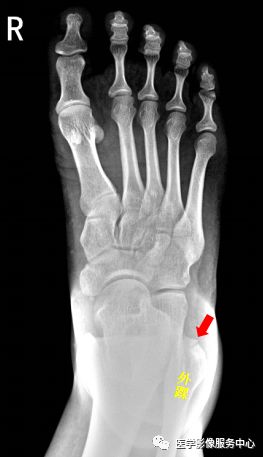

右侧外踝骨皮质连续中断,可见透亮骨折线影,可见软组织稍肿胀影。右踝关节骨折。

Warmreminder: 踝关节扭伤,许多大夫只做踝关节正侧位。有时踝关节正侧位不能看出有明显异常,而有局部软组织肿胀,活动受限时,根据我的经验,踝关节扭伤有时只做正侧位是有局限性的;小妙招足正位也是必不可少的。

此患者就是踝关节扭伤,踝关节正侧位未见异常,加拍足正位时发现外踝骨折。

右足第5跖骨基底部见骨折线,断处稍分离移位。右足第5跖骨基底部骨折。

Warmreminder: 儿童时期足第5跖骨处有骨骺存在,骨骺线易与骨折线混淆,小妙招给你,骨骺线的长轴一般是与第5跖骨长轴平行,而第5跖骨多是横行骨折,换言之骨折线与第五跖骨长轴垂直。